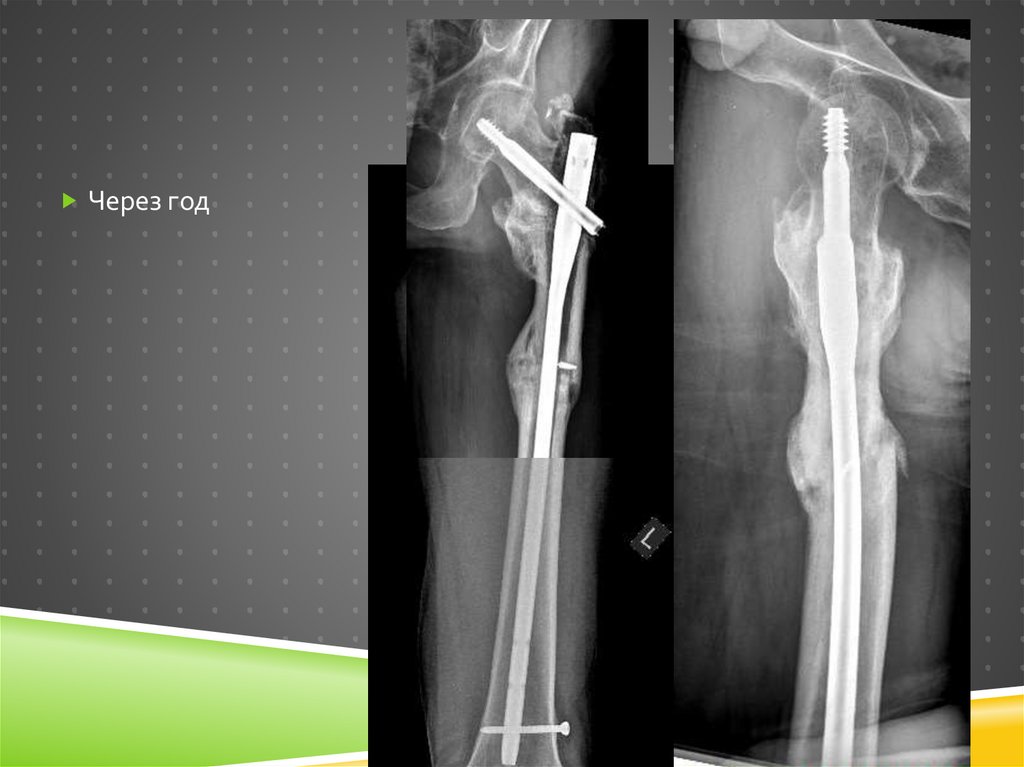

Через полгода…

Что-то пошло не так…

Ревизионный остеосинтез

Уже более правильный

имплантат

Все проблемы решены?